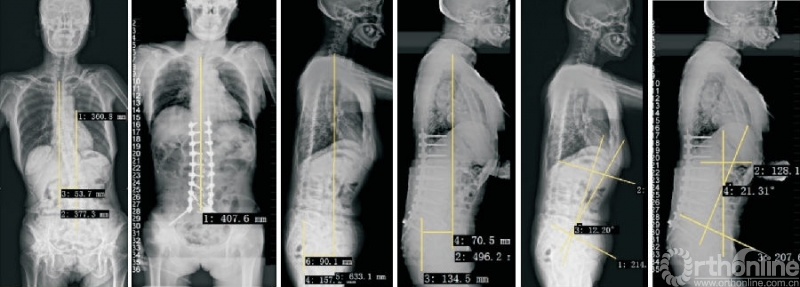

因此,侧方钢板的应用能部分解决这个问题[43]。斜外侧脊柱融合固定系统(PIVOX)(图7)是目前比较成熟的侧方固定方式,已在我科初步应用,用于腰椎节段性不稳定、腰椎椎管狭窄、腰椎侧弯、腰椎盘源性腰痛、邻椎病(图7)等腰椎疾病,截至目前随访结果满意。

图7 PIVOX系统用于邻椎病

初步统计结果显示,相较于经典的OLIF组,PIVOX组并未明显增加融合器沉降、终板塌陷等并发症的发生率。在发挥Stand-alone OLIF优势的同时,保证了脊柱生物力学的稳定性,拓展了Stand-alone OLIF的应用边界。但是,NAYAK等[44]的研究发现,对于侧方脊柱融合术,后路螺钉固定的生物力学稳定性强于侧方钢板固定,因此,当需要刚性、消除运动的稳定时,仍然建议首选后路螺钉固定。

2.4 L5/S1 OLIF

L5/S1节段因血管与腰大肌间隙较窄,过去被认为是OLIF手术的相对禁忌证,但是,越来越多的研究证实,L5/S1 OLIF(图8)是安全可行的,且相较于其他节段,并不会明显增加并发症的发生率或延长住院时间[2,45]。但是,L5/S1 OLIF需要评估血管位置。

图8 L5/S1 OLIF技术

国内第一例L5/S1 OLIF手术于2021年6月在浙江大学医学院附属邵逸夫医院由脊柱外科团队完成,迄今为止已完成了数例该术式,未发生血管损伤、肠梗阻等并发症,其余远期并发症如融合器沉降等尚在随访中。